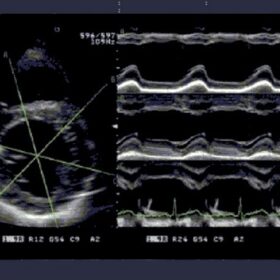

Ultrasound Aloka Prosound SSD-4000 – Image Gallery

FAM (Free Angular M-mode)